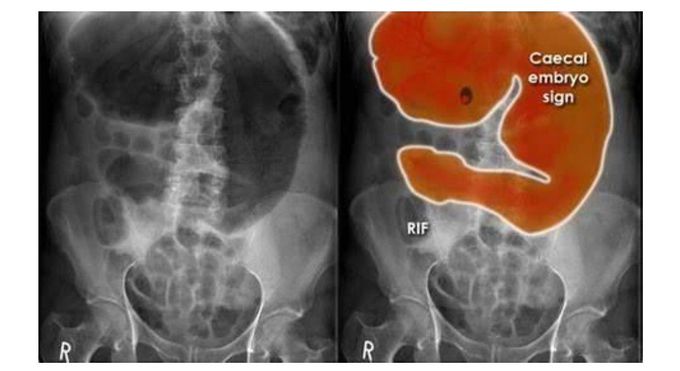

Cecal Empryo sign in Cecal volvulus

Cecal Volvulus

Cecal Empryo Sign